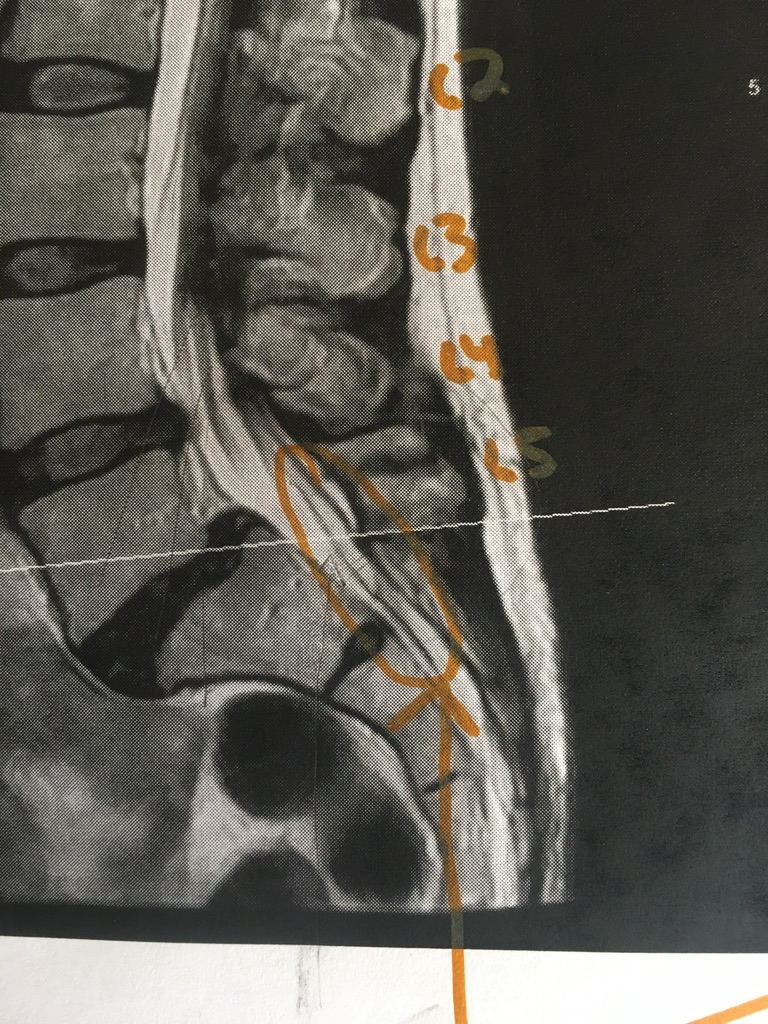

Close-up of the filum. This is what Dr. Klinge cut out and removed. The texture was tough, like grizzled meat, apparently – which is typical of tethered filums.